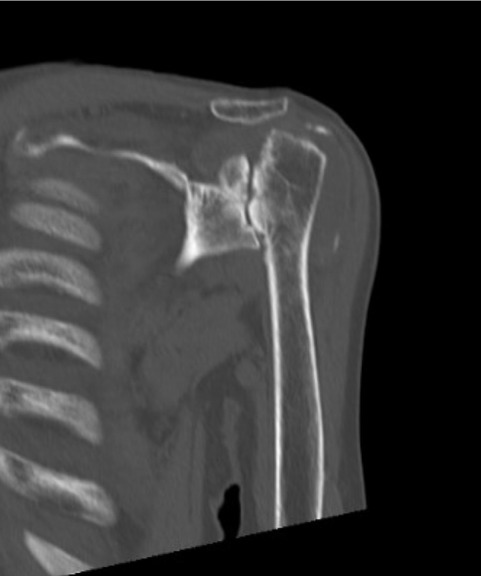

その仕組みを説明します。肩関節は本来、肩甲骨側に受け皿(関節窩[かんせつか])があり、上腕骨の先端にボール状の骨(上腕骨頭)が向かい合う「ボール&ソケット(受け皿)型」の構造をしています。このボールを腱板という筋建で受け皿に固定した状態で、三角筋という大きな筋肉で引き上げることで腕が挙がる仕組みです。一般的な人工肩関節(従来型人工肩関節置換術)では、この解剖学的な構造と同じ向きに人工関節を置き換えます。しかし、腱板が断裂して機能しない肩では従来型の人工関節を入れても、ボールの固定ができないままなので、腕を十分に挙げることができません.リバース型では人工関節の凸凹(ボールと受け皿)をあえて通常と逆に配置します。具体的には、肩甲骨側の関節窩にボール状の人工物をスクリュー固定します.このことでボールは腱板がないままでも既に固定されてしまったことになります.続いて、上腕骨側に受け皿の部品を取り付け、少し腕を下げた状態でボールと受け皿を組み合わせます。こうすることで、三角筋という、残っている大きな筋肉が引き伸ばされ、効率よく力が発揮できるようになります.このように人工物で関節の構造を反転させることで、腱板機能の肩代りを行い、残っている大きな筋肉である三角筋の力を増幅することで腕を挙げられるようになり、さらには可動部分は、神経のついていない人工物になるため、関節面のこすれによる痛みが生じにくくなります。

手術の方法について簡単に説明します。手術は全身麻酔で行い、肩の前方を切開して関節にアプローチします。傷んだ肩関節の骨や軟骨の一部を取り除き、そこに人工関節の部品を固定します。リバース型人工肩関節の人工部品は金属や医療用プラスチック(ポリエチレン)でできており、肩甲骨側にボール状の金属、上腕骨側にカップ状の部品をそれぞれしっかりと設置します。手術時間は肩の状態によって異なりますが、概ね2時間程度で終了します。出血量は通常200〜300ml程度で、輸血が必要になることはまれです。人工関節の設置後、必要な筋肉を修復し手術を終了します。